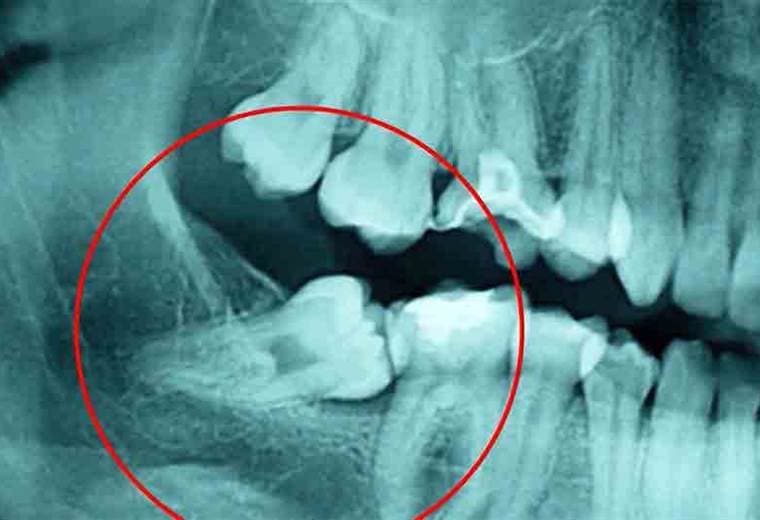

Cuando salen las cordales, es común que presenten síntomas como dolor de cabeza, inflamación y enrojecimiento de la encía

Cuando salen las cordales, es común que presenten síntomas como dolor de cabeza, inflamación y enrojecimiento de la encía.

Algunas de las preguntas que surgen con respecto a la salida de las cordales son: ¿A qué edad deben salir? ¿Siempre duelen? o ¿Por qué a algunas personas les salen y a otras no?